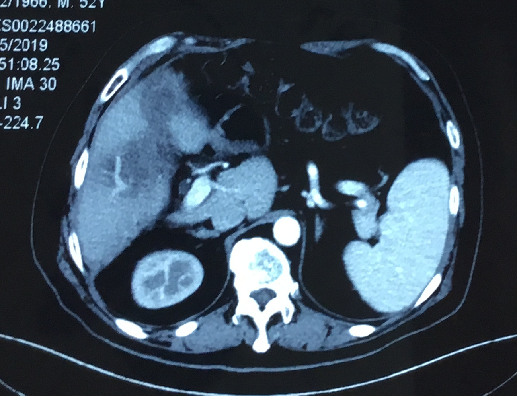

影像学检查:

CT提示:肝多发转移。

2016年12月CT:

2018年04月,CT提示肝转移

2018年11月CT提示肿瘤进展。

2019年01月复查CT提示病情无缓解。

2019年05月复查CT提示病情SD。